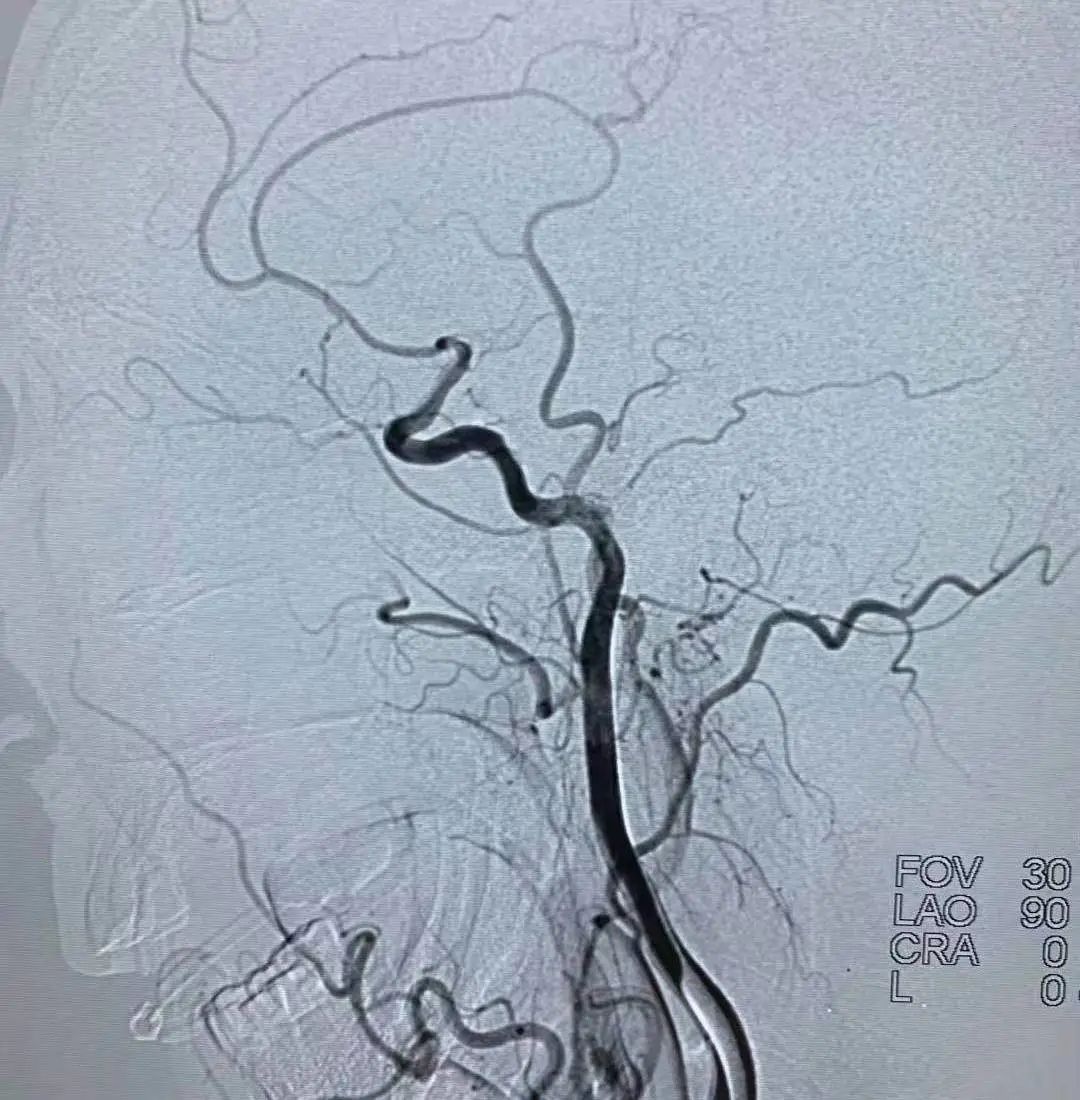

血管内的治疗还包括血管狭窄的治疗,在做头颅磁共振或脑血管造影时,如果发现有血管狭窄,医生就会建议放一个支架,这样就避免了脑梗塞的发生。

近年来,脑血管介入治疗显著提高了闭塞血管的开通率,为静脉溶栓失败和溶栓禁忌的大动脉闭塞患者提供了一种新的治疗选择。但具体诊疗过程中还要因病施治,要根据病人的病情决定什么样的治疗。